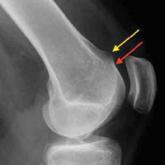

Guidelines for Treatment of Lateral Patella Dislocations in Skeletally Mature Patients

The incidence of lateral patella dislocations is high, particularly in young females. Beside traumatic cases, many patients present with specific...